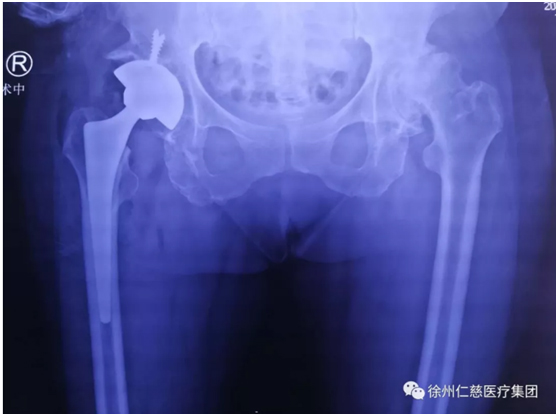

郝醫(yī)生一聽他這么能喝酒,點(diǎn)點(diǎn)頭,安排他攝片,果然,顯示右側(cè)股骨頭壞死,需要做全髖關(guān)節(jié)置換。

昨天,郝亮技術(shù)團(tuán)隊(duì)給李師傅施行了全髖關(guān)節(jié)置換手術(shù),手術(shù)很順利,如今,李師傅正在關(guān)節(jié)病區(qū)康復(fù)。

(術(shù)后)